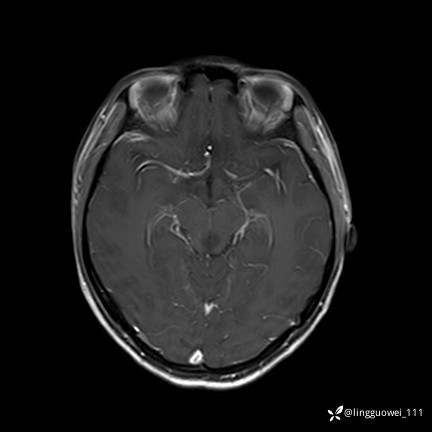

T1增强

img